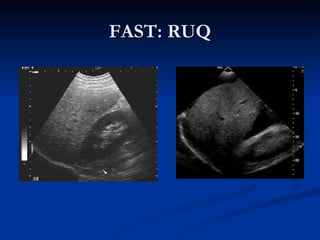

FAST: RUQ